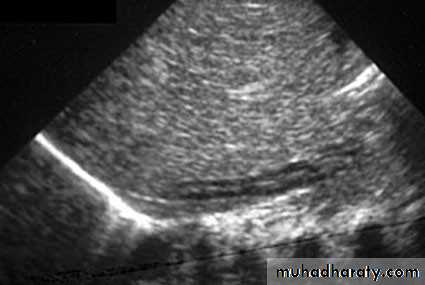

Ultrasound findings:

Division of renal sinus